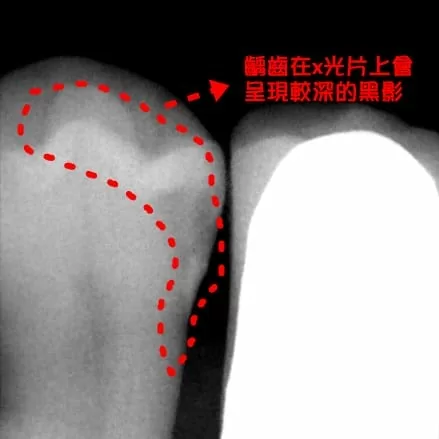

左下第一小臼齒,從牙齒外觀看不出來單側齲齒面積大,但藉由X光片可以清楚判斷(圖一),如果使用樹脂補綴在咬合上擔心容易產生崩落,綜合考量下建議患者採用3D齒雕嵌體,將齲齒部分清除後稍作修形,再使用口內攝像鏡取像,經由電腦繪圖設計後研磨,最後黏著裝置完成。

(圖片)